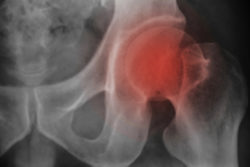

Close up Thigh bone x-rayA couple has filed a Stryker femoral head lawsuit joining a growing multidistrict litigation (MDL) against Howmedica Osteonics Corp. alleging severe adverse effects from the device’s implantation.

Alexander says that he became implanted with an LFIT Anatomic CoCr V40 Femoral Head in his right hip on Dec. 27, 2007 at Miriam Hospital in Rhode Island. He was also implanted with an Accolade TMZF femoral stem in addition to the femoral head, the hip implant lawsuit reports.

The LFIT Anatomic CoCr V40 Femoral Head in addition to the TMZF femoral stem was marketed by the company to promote permanence, durability, and replace worsened and diminished hip bones, increasing hip function and mobility.

However, hazards and problems were reported with the device including issues ranging from hip stem fractures to dissociation of the femoral head from the stem, allowing for insufficient range of motion, and loss of bone fixation strength.

Additionally, other severe injuries included patients having released metal ions, stemming from the junction of the stem component and the LFIT V40 as the metal parts rub together, in their blood stream and surrounding tissue. Patients were able to identify a failing and defective metal-on-metal hip system by checking their blood for levels of cobalt and chromium.